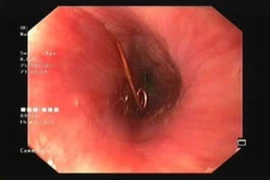

Các bác sĩ Bệnh viện Hữu nghị Việt Nam - Cuba Đồng Hới đã phối kết hợp, thực hiện thành công nội soi phế quản cấp cứu lấy dị vật dưới gây mê cho bệnh nhân 9 tuổi nuốt phải xương cá khi ăn cháo.